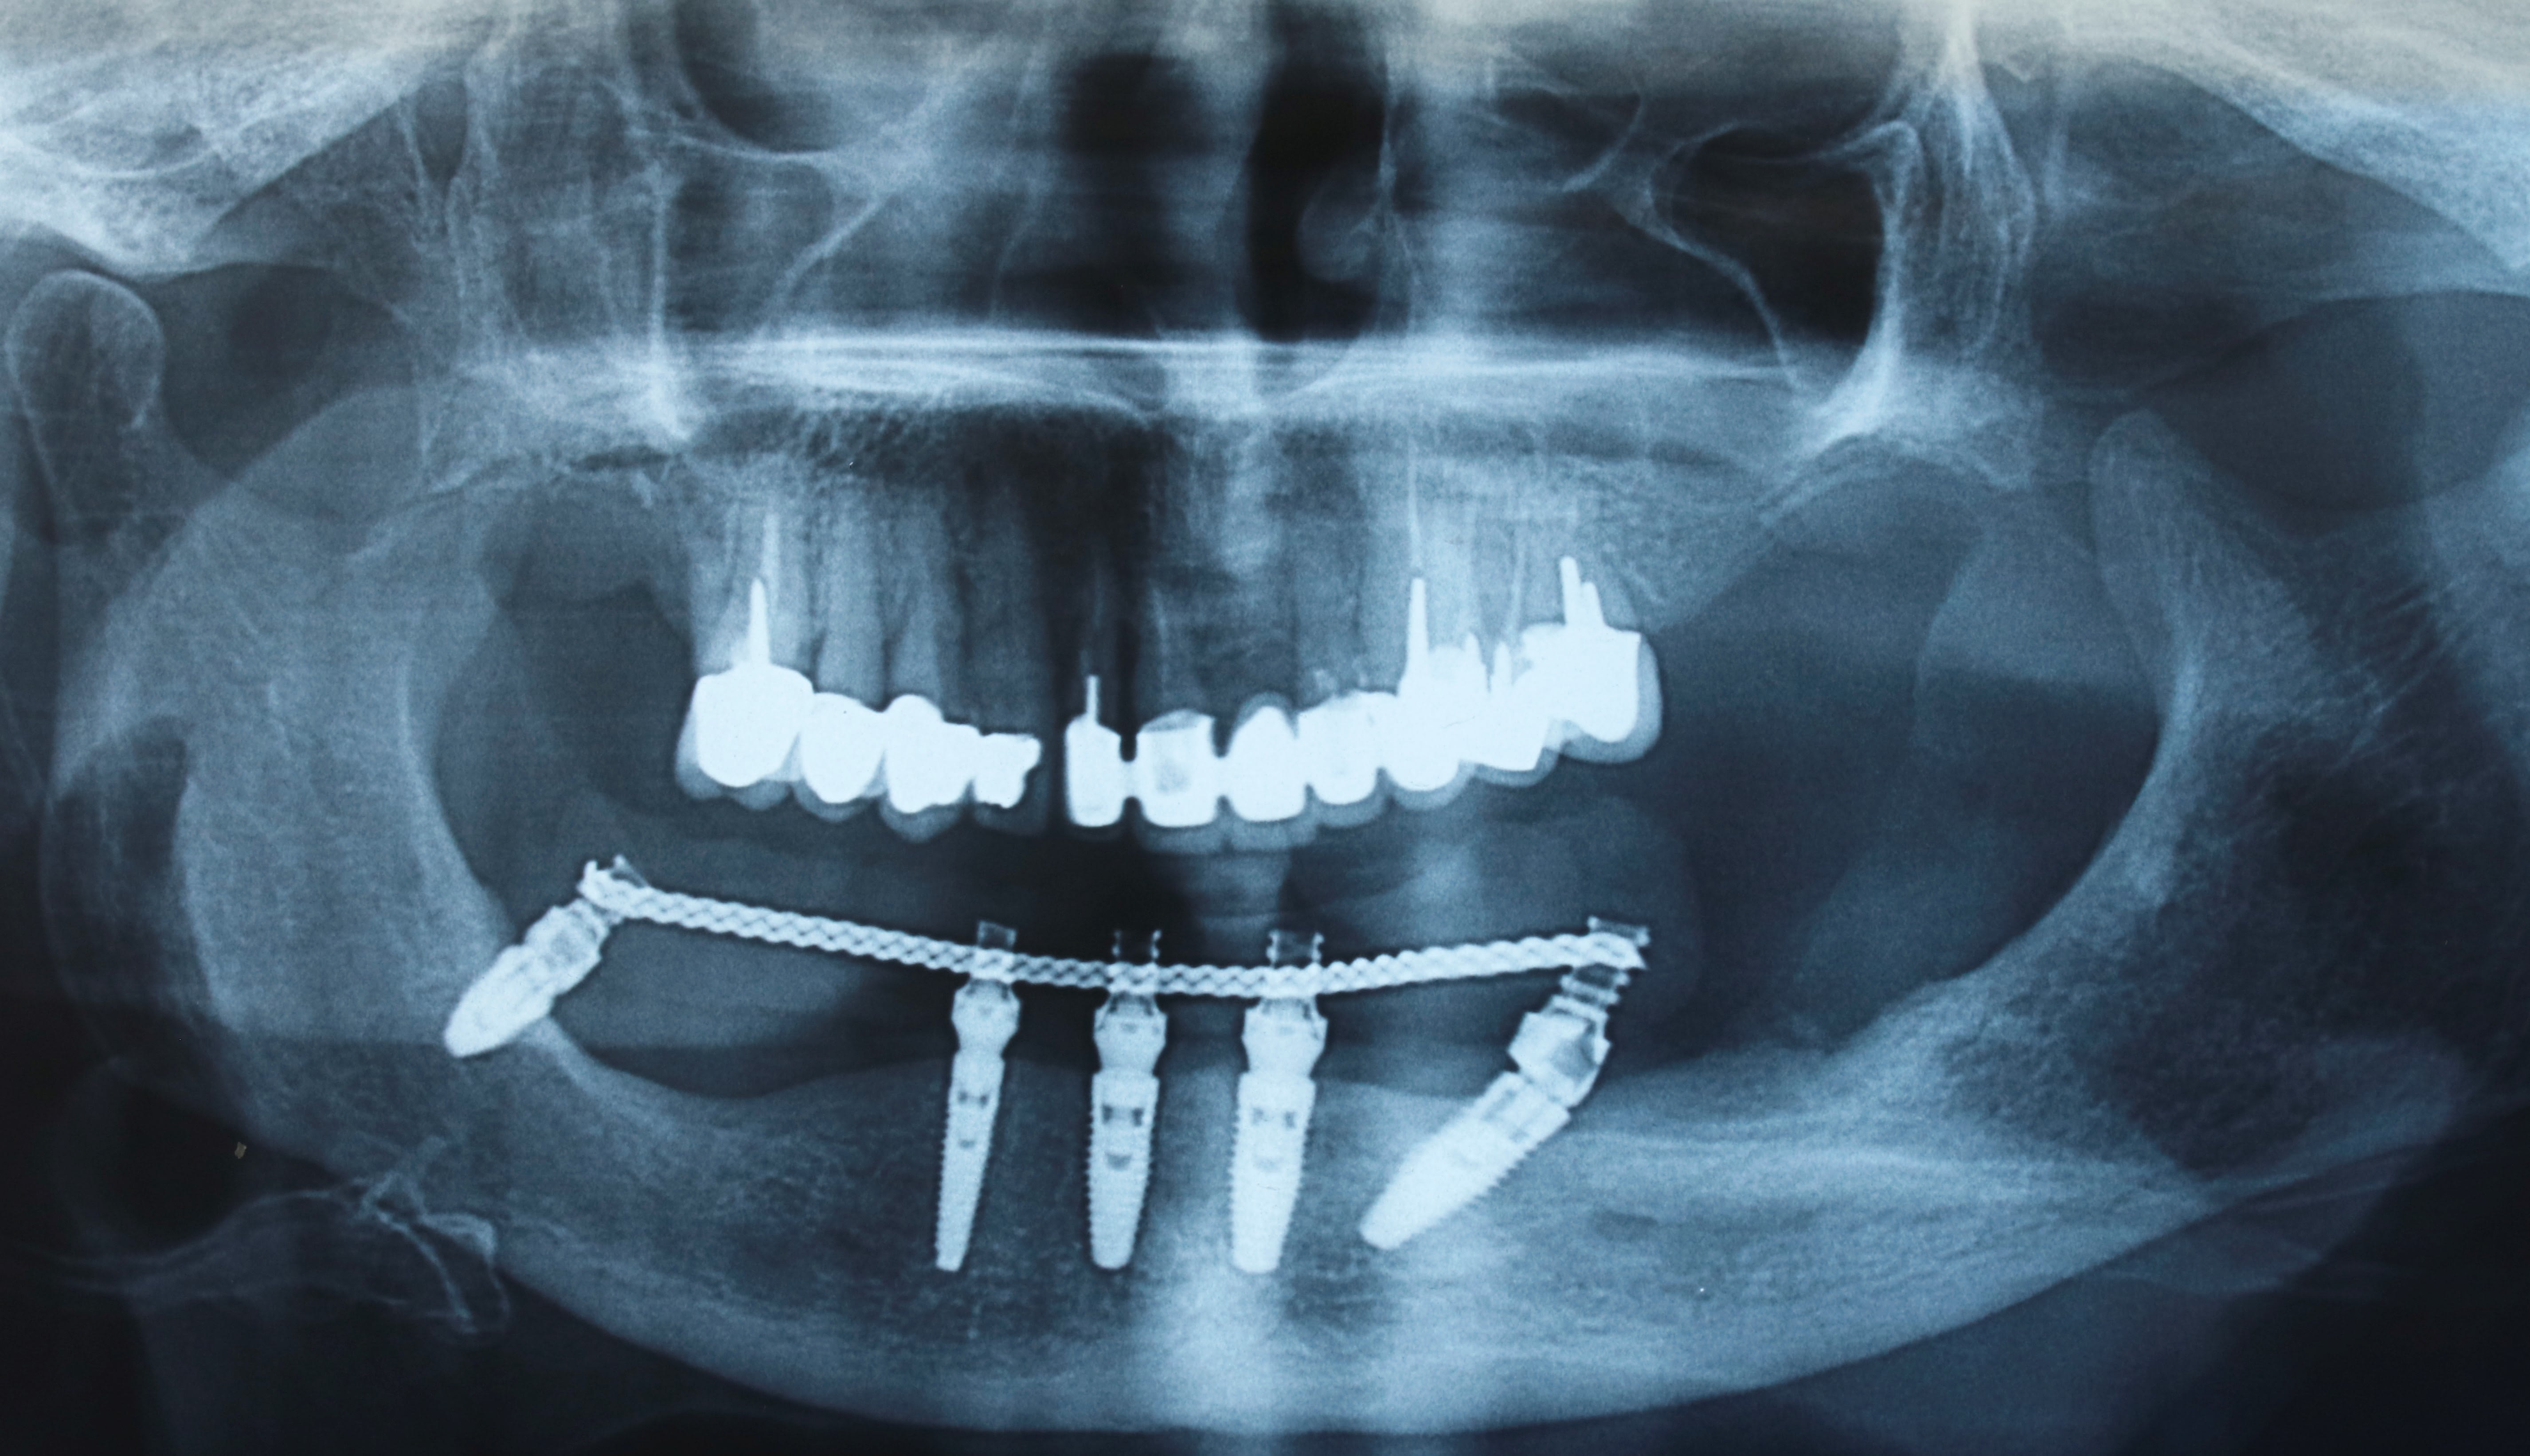

la voilà .

Un implanto qui a du se prendre un trou mentonnier il y a quelques années et depuis il le contourne de loin ;o))

Boucle antérieure.

La mèche rebelle , c'est rare ;o)

A voir avec un CB .

la pano fait peur